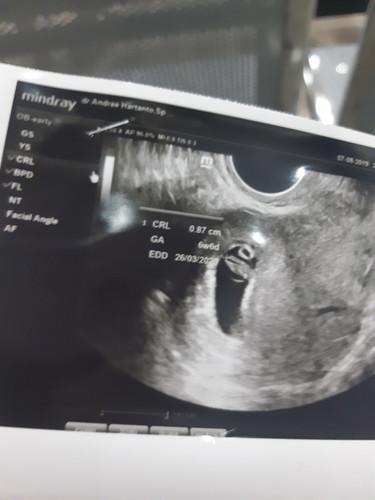

Alhamdulilah ya bun semalam aku usg usia kandungan 6w6d aka 7w.. aku usg transvaginal dan udh kedengeran detak jantungnya...seneng banget... tp kt dokter aku dan suami dilarang berhubungan dulu, trus di kasi penguat kandungan utrogestan. Bunda ada yg diresepin itu juga ga??? Sbnrnya penguat kandungan butuh banget ga sih??? Udh aku tebus sih resepnya selain utrogestan ada bbrp vitamin juga obat antimual, soalny lg lemes2nya ini. Tp mahal bet ya nebus resep sampe 1,2jt..utrogestannya tuh harganya mahal banget. Kl misalny disuruh kontrol lg trus dikasi utrogestan lg tp aku ga ambil kira2 ngefek ga ya ke perkembangan si janin atau kandungan???

Baca lagiAku bangeeet bun, tgl 2juli aku diresepin ini untuk pemakaian 2 minggu itu dan keluar biaya 350rban. Sebenernya habis 550rban tp sisanya admin alkes sama vitamin. Abis itu tgl 14 juli checkup lagi karena obat mau habis dan biaya yg keluar 450rban lebih murah karena obatnya jga cuman 12butir bukan 14butir. Pas checkup tgl 14 juli kehamilan aku 6w1d udah denger detak jantung dede. Diresepin obat yg sama tp beda merk, katanya dikasih obat penguat lg soalnya dalam 12minggu kehamilan itu rentan keguguran. Tp rencananya aku gaakan kedokter lagi, mungkin mau ke bidan aja supaya lebih hemat.